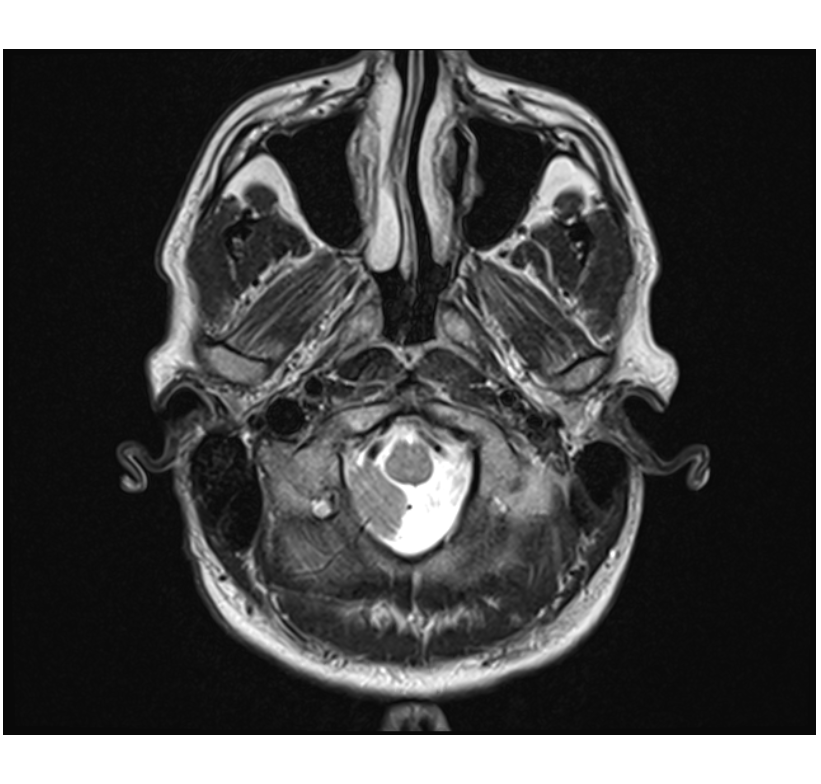

Is this how a lesion looks like?

Help, i finally got an mri, unsure if they checked for ms… this doesnt look normal or is it? help!